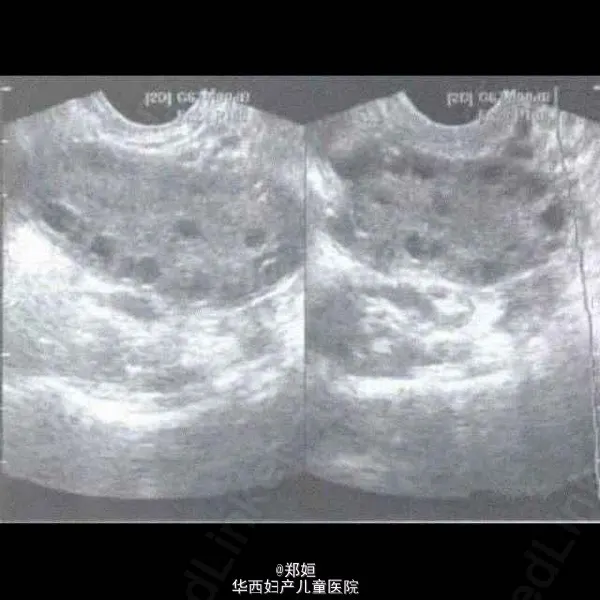

影像学检查是重要的诊断工具之一,经腹部或经阴道B超可发现患有PCOS的患者卵巢中多发性小囊泡排列。在检查中,医生会观察卵巢体积以及囊泡数量是否符合典型的“多囊卵巢”特点。